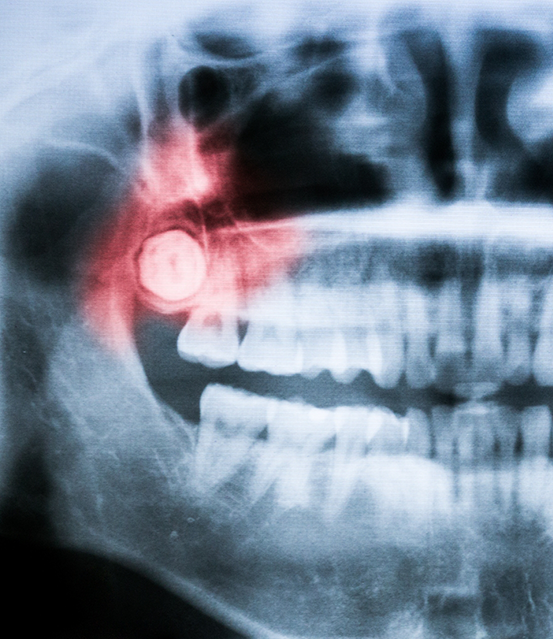

At Titanium Dental of Fort Worth, your comfort and safety are our top priority. We use CT scanning to get a detailed 3D image of your jaw. This helps us:

- Identify the exact location of your wisdom teeth

- Evaluate how close the roots are to your nerves and sinuses.

- Plan the most efficient wisdom teeth removal.